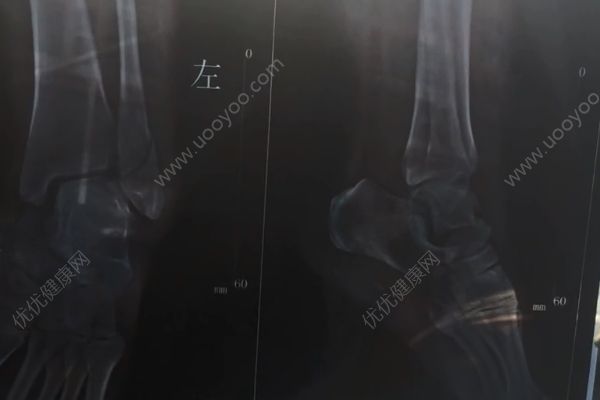

医患关系近几年来比较紧张,和很多因素有关,有些患者不理解医生,有些医生没有尽职尽责,导致医生和患者之间有许多矛盾,在江苏的一位女士,明明是左脚骨折了,但是医生做手术的时候出现错误,将她的右脚开刀了,出现这种错误,医生有很大的责任。

江苏,姚女士左脚骨折,医生竟然把没有受伤的右脚开刀做了手术。“怎么还买一送一?”姚女士懵了,找医生理论。医生称,常在河边走哪有不湿脚的,“行医这么多年我也没见过不犯错的医生”。